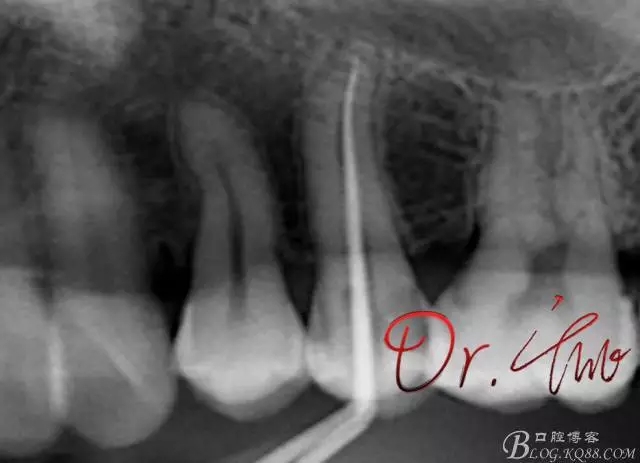

試主尖,近中頰側(cè)形成臺階

640.webp (7).jpg

試主尖,近中頰側(cè)再次拍片查看臺階位置及確定長度

640.webp (8).jpg

試主尖,近中頰側(cè)試主尖,此時手用銼02錐度的已擴到30號,可以明顯感覺到臺階位置,挫預(yù)彎后找好正確位置可順利到達根尖,但是機用銼就是下不去,也是郁悶